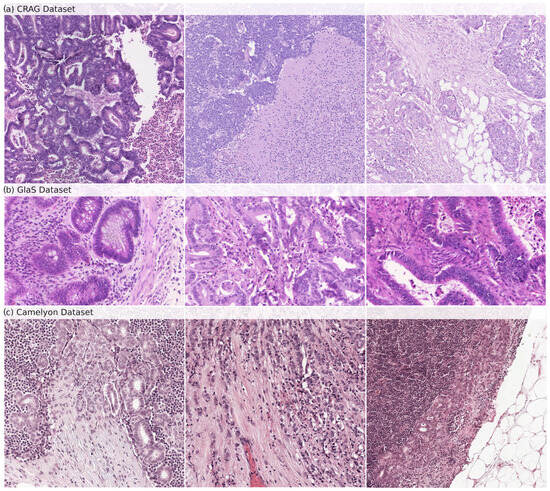

The CRAG dataset [22] is our model’s internal training and validation foundation. It consists of 213 H&E-stained histopathology images, specifically on colorectal adenocarcinoma tissues. The dataset is divided into 173 images dedicated to training the model and 40 images for testing its accuracy. Each image is annotated at the pixel level to delineate the glandular structures precisely. This detailed annotation allows a robust evaluation of the model’s gland segmentation capabilities. At the same time, the image resolution varies within the dataset, typically around 20× magnification. Samples from the CRAG dataset can be seen in Figure 1a.

Figure 1.

Samples of histopathological images from (a) CRAG, (b) GlaS, and (c) Camelyon datasets. These images show the diverse glandular structures and tissue types present in each dataset, which are used for training (CRAG) and evaluating (GlaS and Camelyon) GB-SAM.

We selected the GlaS and Camelyon16 datasets to evaluate GB-SAM trained on CRAG.

GlaS Dataset: The GlaS dataset [23], an external testing benchmark, enhances the generalizability of our model’s performance beyond the training data. It offers 165 H&E-stained images derived from colon tissue sections, providing a broader range of histological features compared to CRAG. The dataset is divided into 85 training images and 80 testing images. Like CRAG, images are meticulously annotated at the pixel level to identify glandular structures. The GlaS dataset is a popular choice for evaluating gland segmentation algorithms due to the exceptional quality of its annotations and the inclusion of images with diverse gland morphologies, reflecting the variations observed across different histological grades. This variety ensures that the model encounters broader challenges during testing. Samples from the GlaS dataset can be seen in Figure 1b.

Camelyon16 Dataset: The Camelyon16 dataset [24] is important in assessing our model’s ability to detect lymph node metastasis in breast cancer patients. It includes a collection of 400 whole-slide images (WSIs) obtained from sentinel lymph nodes, the first lymph nodes to receive drainage from a tumor site. The dataset is further split into 270 training slides and 130 testing slides. Each WSI is annotated to mark the exact regions containing metastatic cancer cells. Samples from the Camelyon dataset can be seen in Figure 1c.